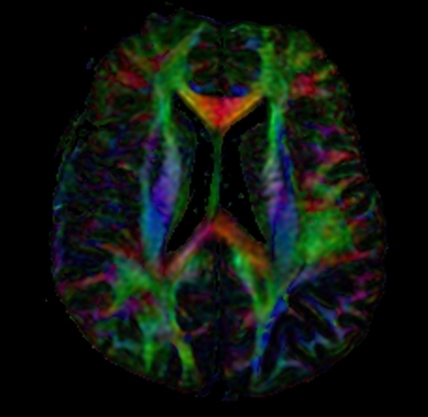

Diffusion Tensor Imaging (DTI)

Diffusion Tensor Imaging (DTI) shows white matter tracts in brain tissue. These tracts allow different parts of the brain to talk to each other. Think of the brain as if it were a computer. With DTI, doctors can see and measure the "cables" connecting parts of the brain. DTI can provide information about damage to parts of the nervous system as well as about connections among brain regions.